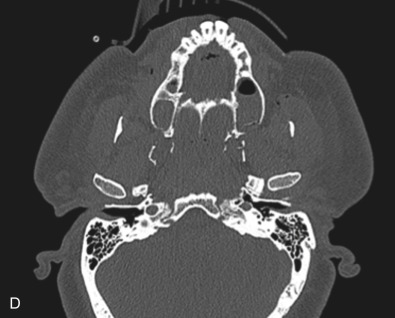

Le Fort III fractures generally consist of a combination of fractures that involve the palatine bones, the maxilla, the pterygoid plates, the nasal bones, lacrimal bone, and zygomas; they essentially separate the face along the base of the skull. The fracture pattern extends through the nasofrontal suture along the medial wall of the orbit, through the inferior orbital fissure and the lateral orbital wall to the zygomaticofrontal suture. In addition, the zygomaticotemporal suture is separated. The fracture extends across the sphenoid bone resulting in dysjunction at the pterygoid plates ( Figs. 1.13.16 and 1.13.17 ). The septum is separated from the cribriform plate of the ethmoid. Pure Le Fort III fractures are rare, and in actuality, most are ZMC fractures in conjunction with Le Fort I and II fractures lending the appearance of a comminuted “Le Fort III.” The force is delivered from the orbital level, resulting in craniofacial dysjunction. The fracture is generally more comminuted and more extensive on the side of force application.